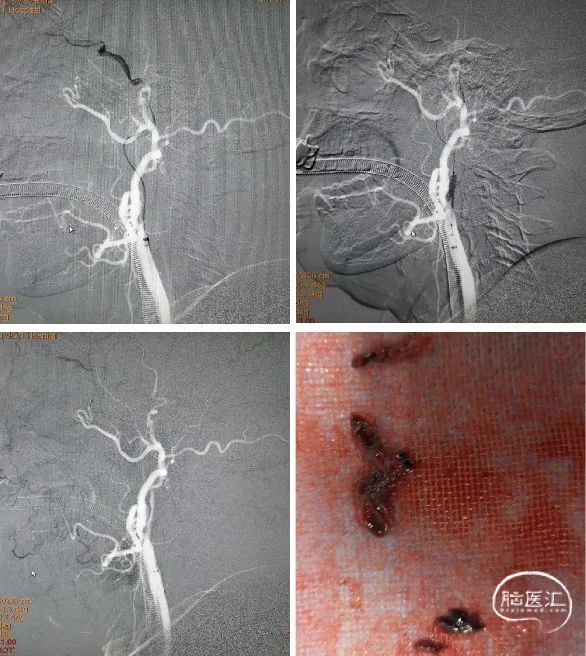

将Reco 4*20mm取栓支架送入血栓处,支架释放5min后,中间导管连接50ml注射器负压抽吸,撤出支架,成功拉出血栓。再次造影显示大脑中动脉M1段开通,但血管壁毛糙明显,经中间导管推注替罗非班7ml避免内膜损伤急性血栓形成。

替罗非班经静脉7ml/h维持,10min后经导引导管于颈总动脉造影显示:颈内动脉起始部重度狭窄,远段血通畅,(mTICI评分3级)。为降低风险,决定二期处理颈内动脉狭窄。

术后2月来院复查造影:左侧颈内动脉起始部狭窄严重,左侧大脑中动脉M1段血流通畅。予以植入颈动脉支架。